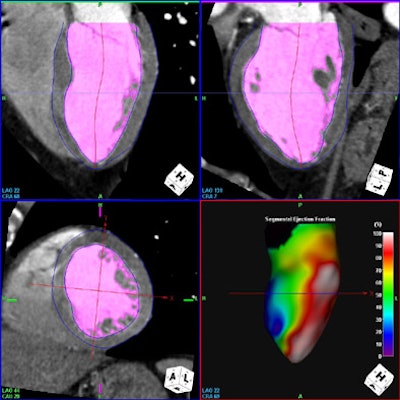

![]() |

| All images were acquired in a 62-year-old man presenting to the hospital for evaluation of chest pain. CT-based assessment of cardiac function with akinesis of the anteroseptal wall, indicated by dark cold spectrum colors in an automatically generated functional model of the left ventricle. |